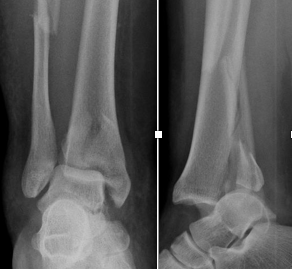

Artroplastia Total do Tornozelo

Cirurgia de substituição articular para tratamento da Osteoartrose do Tornozelo